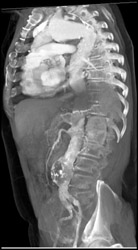

Celiac Artery Aneurysm